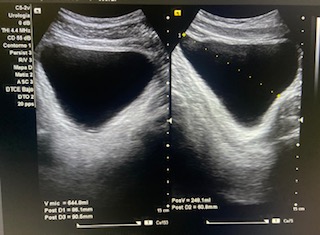

Volumen residual: 243 ml. Próstata de contornos regulares y ecogenicidad homogénea a simple vista. Volumen prostático: 49 cc.

En ecografía determinamos el tamaño de la próstata mayor de 20 cc, por tanto se trata de una HBP grado II. La medición del RPM nos permitió detectar que el paciente presentaba residuos elevados (243 ml).

Nueva ecografía de control en seis meses se recomienda segunda determinación dada la variabilidad de la prueba en el estudio de RPM y control clínico de STIU a pesar del tratamiento.